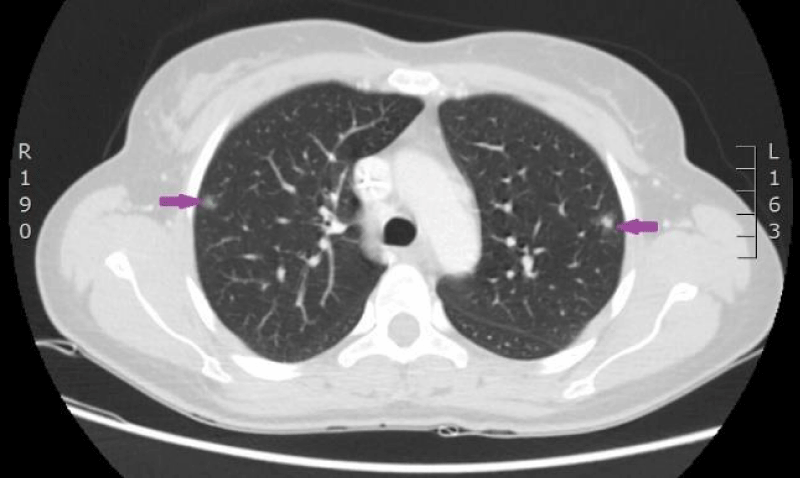

The woman was admitted to P. Stradins CUH on 6th June 2016 for continuation of chemotherapy. Control analyses and computed tomography were performed, and positive dynamic was observed again, however septic pulmonary emboli bilaterally were observed (Figures 11,12). Growth of Burkholderia cepacica in the venous access port CELSITE was repeatedly detected, so the port was evacuated on 7th June 2016.

Figure 11: 11.06. 2016. Computed tomography of lungs. Presence of septic emboli in both lungs (CT scan from Diagnostic Radiology Institute of P.Stradins CUH).

Figure 12: 11.06. 2016. Computed tomography of lungs. Presence of septic emboli in both lungs (CT scan from Diagnostic Radiology Institute of P.Stradins CUH).